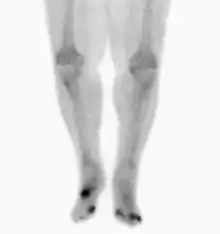

| Osteomyelitis of the 1st toe | |